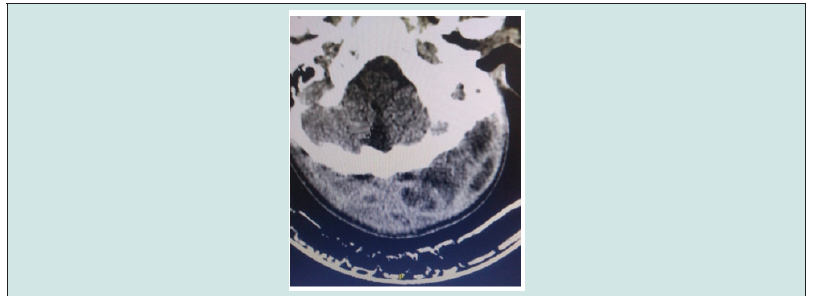

A male 18 year-old teenager was admitted to the João Lúcio Pereira Machado Hospital and Emergency Room on March 08, 2022 with a purulent otitis externa in the left auditory conduit associated with fever, asthenia, weight loss, and anemia for about 15 days. He evolved with extensive inflammatory lesion with a floating zone extending from the left retroauricular region and parieto-occipital associated with periorbital edema and left ptosis, claiming a history of intermittent mucopurulent otitis not treated since his 15 years of age. He was in regular general condition, eupneic, dehydrated, febrile, presenting cutaneous pallor, hypotension of 96/49 mmHg and tachycardia of 160 bpm, but referring to otalgia and intense headache. He was hospitalized for 3 days at the Presidente Figueiredo Hospital, with the use of the ceftriaxone medication, and the clinical picture persisted. After a hypothesis of chronic otitis media with the presence of mastoiditis and extensive scalp abscess was raised, a CT (Figure 1) was performed on 08/03/2022 showing an inflammatory otomastoidopathy and the presence of hypodense collections that corresponded to a voluminous abscess that extended from the posterior cervical region to the bilateral parieto-occipital region, accentuated on the left. The first leukogram, performed in the municipality of origin, was within the normal range with an alteration of the erythrocyte demonstrating hemoglobin of 10.2 and hematocrit of 29.6 g/dL. In a new hemogram performed on 08/03/2022, it showed a leukocytosis level of 13,300 mm³ with 80% segmented, hemoglobin of 9.2 g/dL and hematocrit value of 26.7 g/dL. From the hemogram performed, showing a hemoglobin content of 8.0 g/dL and hematocrit of 24.9 g/dL and a PCR of 180 mg/dL, broad-spectrum antibiotic therapy (ceftriaxone and clindamycin) was initiated, associated with venous hydration, transfusion of hemoconcentrate (02 units) and symptomatic treatments, with submission of local anesthetic to drain the scalp abscess with an approximate output of 300 mL of pus-like secretion of yellowish- greenish color and fetid odor. Using a Penrose drain (Figure 2) due to the extension of the necrotic area, it was observed that, shortly after drainage, a partial reversal of the palpebral ptosis occurred, where we concluded that the cause of it occurred due to compression of the facial nerve by the large volume of secretion at the mastoid level. The patient evolved with clinical improvement from antibiotic therapy. He was discharged improved after physiological erythrocyte patterns were reestablished.

Figure 1: CT scan of skull showing inflammatory otomastoidopathy and presence of hypodense collections.